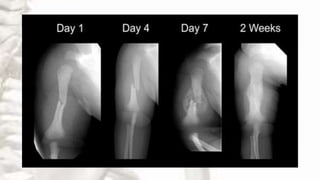

Stages of bone healing

HAEMATOMA INFLAMMATION CALLUS CONSOLIDATION REMODELLING

Stages of bonehealing HAEMATOMA INFLAMMATION CALLUS CONSOLIDATION REMODELLING